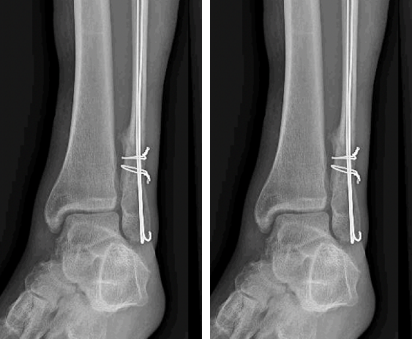

fracture de la cheville (péroné distal)

Publié par : docteur Jean pierre Lechalivier